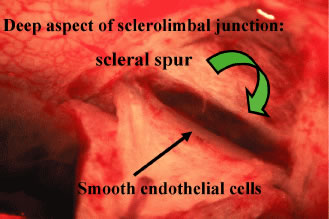

is not within the tissue to be cut by the scissors. Tenon's capsule, with its conjunctiva, is spread anteriorly over the

cornea to give the best view possible of the corneal scleral sulcus. In

almost all instances, there is a thin layer of episclera remaining. This

layer is grasped and elevated forcibly, permitting development

of a 2 × 2-mm buttonhole, through which the bare sclera is easily

visible. This episcleral tissue is markedly adherent. The buttonhole

should be extended approximately 5 mm temporally and laterally. The

forceps are used to grasp the edge of this deep episcleral tissue, and

pull it anteriorly and inferiorly, so the surgeon can clean down to bare

sclera anteriorly to the corneoscleral sulcus. The sulcus is not readily

visible until the episcleral tissue has been reflected from it. In

fact, it probably is the single most important landmark with regard

to filtration surgery. As seen in Figure 4, the conjunctiva inserts just anteriorly to the corneoscleral sulcus. Dissection